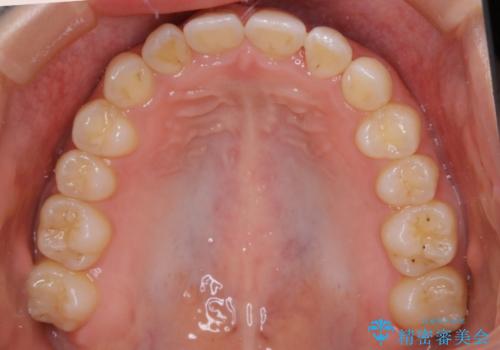

- 前から2番目の歯が捻じれていることが気になるとご相談にいらした方です。

インビザラインFULLで治療を行いました。

上の前から2番目の歯は、一般的に周囲の歯と比べて小さく、動きづらい歯であると言われています。前歯にゴムかけを行うことで理想的な位置まで歯を動かしてくることが出来ました。